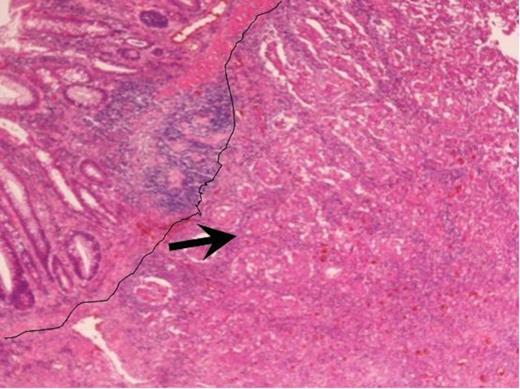

Immunohistochemistry showed tumour cells to be negative for CEA and CK 20, but was strongly positive for CK7 (Figure 4 & 5). The tumour also showed focal positivity for ER and was negative for both progesterone receptor (PR) and Human Epidermal Growth Factor Receptor 2 (Her2). After comparing the morphological and immunohistochemistry charachteristics of the primary breast cancer and rectal tumour, the pathologist concluded that the features were consistent with a primary breast cancer metastasising to the rectum. She underwent an uneventful post-operative recovery and remains disease free during her follow-up until now.

Immunohistochemistry staining of the resected tumour. CK 20 immunohistochemistry positive normal large bowel mucosa with the adenocarcinoma being negative (magnification × 4).

Immunohistochemistry staining of the resected tumour. Arrows identifying positive CK7 staining within tumour (magnification × 4).